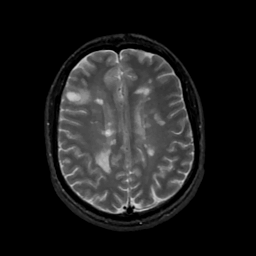

MR Study #7, March 24, 1991 -- Slice #33